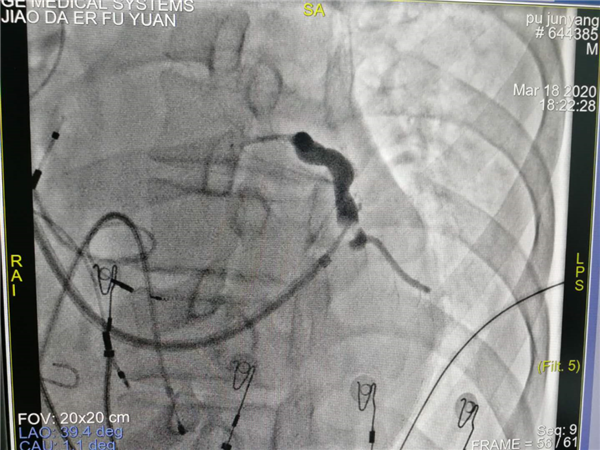

团队术前缜密讨论,充分考虑多个结局,多种策略。手术由郑强荪主任,韩振华副主任,薛嘉虹副教授,王新宏副教授及导管室护士王军、杨宏斌共同完成。团队先为患者行左心室电极植入冠状静脉窦的经典CRTD,但患者冠状静脉窦分支条件较差,左侧后支迂曲盘旋,给操作带来极大的困难,经多次尝试左室电极仍不能植入成功,郑强荪主任、韩振华副主任带领的团队迅速改变策略,与时俱进,决定行左束支区域起搏。另外患者在拔除原右室电极时又因电极与上腔静脉入口处粘连拔除困难,再次为手术带来障碍,最终经团队6小时的不懈努力,手术顺利完成。术后心电图QRS波群由原来的210ms缩窄为160ms,患者心功能明显改善。

术中冠状静脉窦造影